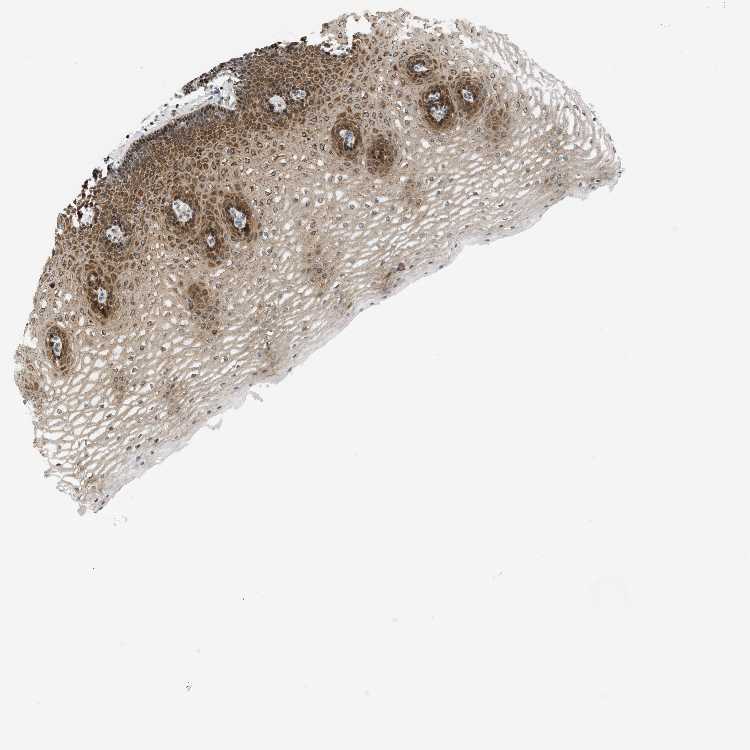

ESOPHAGUS - Antibody stainingi

Antibody staining in the annotated cell types in the current human tissue is reported as not detected, low, medium, or high, based on conventional immunohistochemistry profiling in selected tissues. This score is based on the combination of the staining intensity and fraction of stained cells.

Each image is clickable and will lead to virtual microscopy that enables deeper exploration of all samples and also displays staining intensity scores, fraction scores and subcellular localization as well as patient and tissue information for each sample.

Antibody CAB020139

Squamous epithelial cells Medium